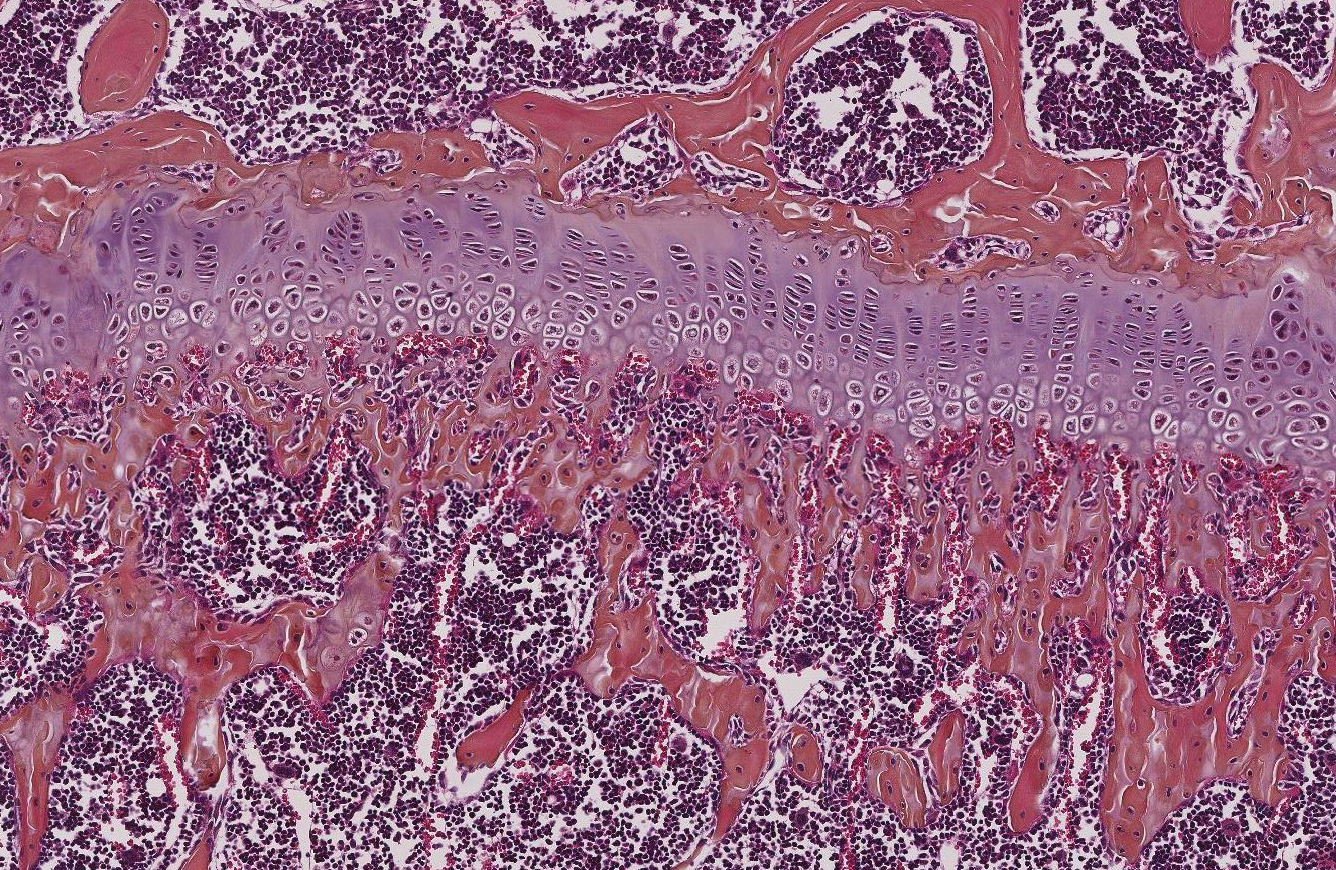

The Cassat Lab studies host-pathogen interactions during invasive bacterial infection, with a special emphasis on understanding how infection and inflammation perturb musculoskeletal cell biology. Osteomyelitis (bone infection) is one of the most common invasive bacterial infections in children, and it also occurs frequently in adults after trauma or surgery. The bacterial factors that promote survival in the bone, as well as the host factors that protect from osteomyelitis, are poorly defined. We have developed a variety of tools to understand how bacteria and inflammation trigger changes in bone biology, including a murine model of Staphylococcus aureus osteomyelitis, high-resolution 3D imaging of bone remodeling, and cell culture models of osteoblast and osteoclast proliferation and function.